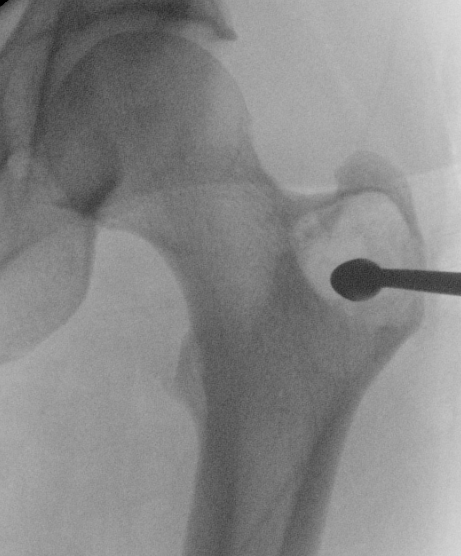

Radiofrequency ablation

Indication

- small

- joint surface not at risk

Results

- 25 cases treated with RF ablation

- 88% of patients became asymptomatic

Kulkarni et al J Vasc Interv Radiol 2021

- 27 cases treated with RF ablation

- 93% complete pain relief at 6 weeks

- 2 cases developed osteonecrosis and joint space collapse